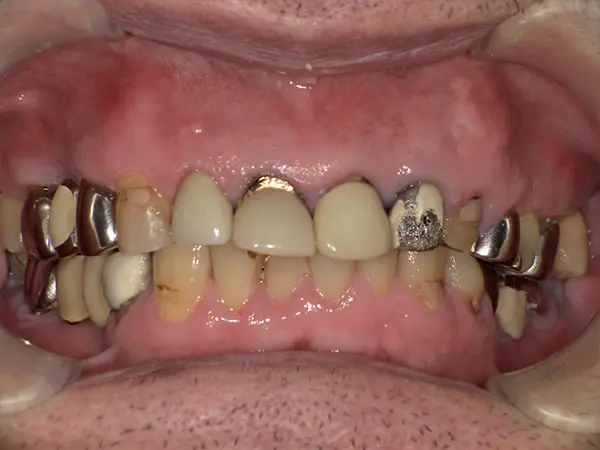

叢生・反対咬合

術前正面

術中正面

術後正面

術前上顎

| 主訴 | 歯のでこぼこ |

|---|---|

| 診断名あるいは主な症状 | 叢生、反対咬合 |

| 初診年齢 | 45歳 |

| 治療内容・装置 | マルチブラケット装置(上下表側からの矯正治療) MSE2 |

| 抜歯・非抜歯 | 下顎左第二小臼歯抜歯 |

| 治療期間 | 2年9ヶ月 |

| 費用 | 882,700円(税込) |

| 治療のリスク・副作用 | 歯の移動に伴う痛み 上下顎前歯部の歯根吸収 装置による口内炎 ブラッシング不良によるむし歯、歯周炎 |